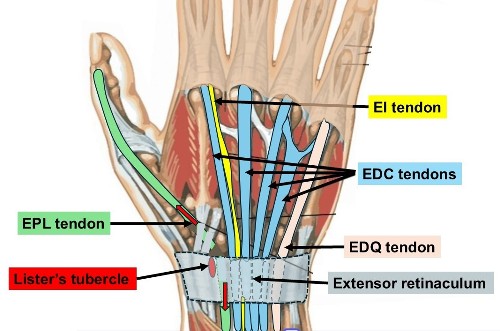

- The EPL = Extensor Pollicus Longus tendon runs along the back of the wrist to the thumb and wraps around Lister’s tubercle, using it as a pulley.

- The muscles are in the forearm. Tendons are like rope joining the muscles to the fingers and thumb. There is a strap of tissue ( extensor retinaculum) on the back of the wrist that holds the tendons down. There are 6 tunnels on the back of the wrist containing the Extensor tendons to the thumb, fingers & wrist.

- This applies particularly when the fracture involves Lister’s tubercle – a prominence on the back of the radius around which the EPL changes direction

- There are 2 tendons that extend the Index finger ( EI & EDC tendons)

- The EI tendon is available for transfer because the EDC tendon to the index finger can still provide normal index finger extension on its own

- The Extensor Indicis (EI) tendon (used to extend the index finger) is redirected to take over the function of the EPL.